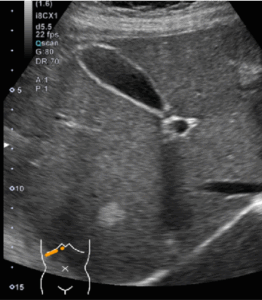

肝血管腫は健診を受けた人の約7%に見られ、女性にやや多い傾向があります。小さいものはエコーで境界がはっきりとした白いしこりとして観察されますが、大きくなると白さが淡くなることがあります。肝血管腫は血管が海綿状に合ったもので、皮膚でいうと「あざ」のようなものです。基本的には無症状で経過観察だけで大丈夫と考えられています。

しかし、エコーで白さが淡かったり、黒い部分が混在している場合は、一度造影CT検査をお勧めしています。造影CT検査では、しこりの周辺から染まっていき、時間がたつと全体が染まるという典型的な像がみられるので容易に診断できます。ごく稀に出血したり、早期がんで徐々に大きくなることがあるので、年に一度は腹部エコーで経過観察することをお勧めします。